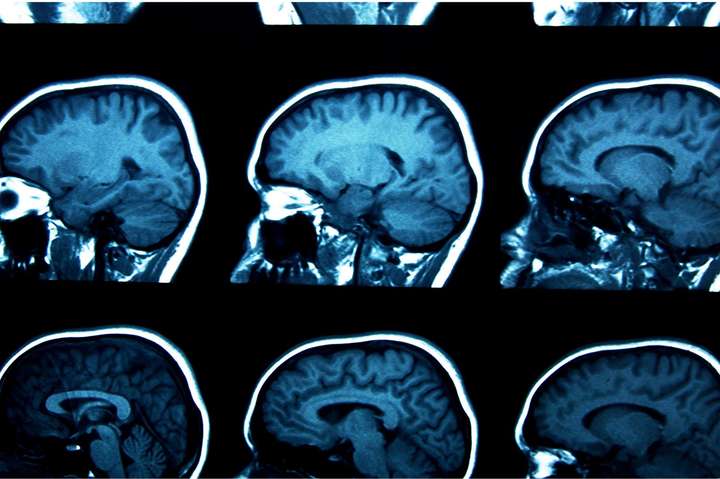

Хосе Кармена (Jose Carmena) из Калифорнийского университета в Беркли и его коллеги продемонстрировали новые грани удивительной пластичности головного мозга. Им удалось натренировать нейроны, обрабатывающие визуальную информацию, выполнять моторные функции. glavnoe.ua »

Исследователи "научили" сенсорные нейроны активности моторных. zn.ua »

Эксперименты на грызунах продемонстрировали пластичность мозга, позволив “научить” сенсорные нейроны активности моторных.